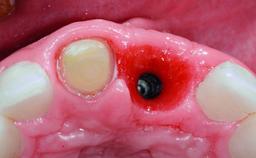

A 32-year-old female Caucasian patient with a compromised maxillary right central incisor was referred to us by a general dentist. Her chief complaints were discomfort and mobility of tooth 11 with unsatisfactory esthetics due to discoloration. The patient reported a previous trauma, some years earlier, as the origin of pathology on the afflicted tooth. Anamnesis was negative for any other dental or periodontal pathology in the remaining dentition. The patient did not take any medication and reported to be a light smoker (5–10 cigs/day). She had high esthetic expectations of her treatment. The extraoral examination revealed a high smile line with full exposure of her maxillary teeth and surrounding soft tissue in the area between the second premolars.

Bone Augmentation Horizontal|Simultaneous|Staged

Augmentation Materials Autogenous chips|Xenogenous|Membrane